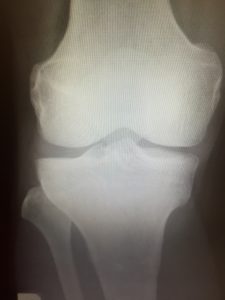

Q5,画像検査で痛みの原因がわかる